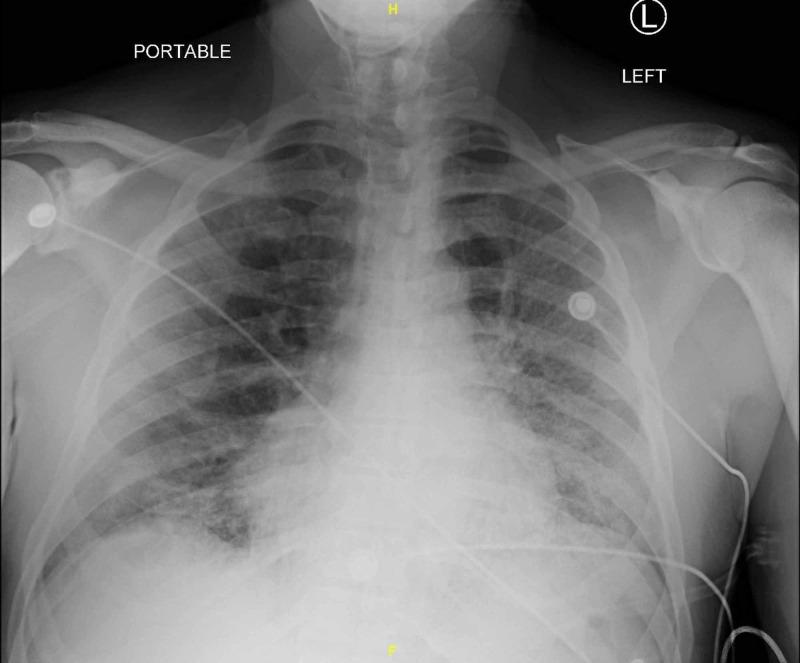

Coronavirus disease 2019 (COVID-19), caused by severe acute respiratory syndrome coronavirus 2 (SARS-CoV-2), has been found to cause multiple complications across several organ systems in patterns not typically observed in previous iterations of the virus. Hemostatic mechanisms have been noted to be significantly altered in particular, resulting in a disseminated intravascular coagulation (DIC)-like picture with elements of coagulopathy as well as hypercoagulability. A 65-year-old man with hypertension, hyperlipidemia, prior tobacco use, chronic kidney disease, and diabetes presented from a correctional facility with hypoxia. The diagnosis of COVID-19 was confirmed. With his elevated D-dimer of >7,955 ng/mL (reference: 90-500 ng/mL) in the setting of COVID-19 and hypoxia, he was empirically started on therapeutic anticoagulation with enoxaparin. His oxygen requirements increased, mental status deteriorated, and platelets began falling, raising concern for heparin-induced thrombocytopenia versus DIC. Heparin products were discontinued in favor of a direct oral anticoagulant. He later became obtunded and unable to tolerate oral medications. Fondaparinux was initiated. Two days later, he was found to have acute limb ischemia of the right lower extremity. He underwent surgical thrombectomy but required an above-the-knee amputation the following day. Shortly after he died secondary to hypoxic respiratory failure. This case highlights the derangement of hemostatic mechanisms seen prominently in COVID-19 infection and raises questions as to appropriate anticoagulant choices to adequately prevent thrombosis. Thorough physical exams should be performed on all patients with COVID-19, taking into account this documented hypercoagulability. Further investigation is warranted into the use of heparin products as the anticoagulant of choice in these patients given observed deficiencies of antithrombin III (ATIII).

2019冠状病毒病(COVID-19)由严重急性呼吸综合征冠状病毒2(SARS-CoV-2)引起,已发现会导致多个器官系统出现多种并发症,其表现形式在该病毒的先前变种中并不常见。尤其值得注意的是,止血机制发生了显著改变,导致出现类似弥散性血管内凝血(DIC)的情况,伴有凝血病和高凝状态的特征。一名65岁男性,有高血压、高脂血症、既往吸烟史、慢性肾脏病和糖尿病,从一所惩教机构因缺氧前来就诊。COVID-19诊断得到证实。鉴于其在COVID-19和缺氧情况下D-二聚体升高至>7955 ng/mL(参考值:90 - 500 ng/mL),经验性地开始使用依诺肝素进行治疗性抗凝。他的氧气需求增加,精神状态恶化,血小板开始下降,这引发了对肝素诱导的血小板减少症与DIC的担忧。停用肝素类产品,改用直接口服抗凝剂。他后来变得意识模糊,无法耐受口服药物。开始使用磺达肝癸钠。两天后,发现他右下肢出现急性肢体缺血。他接受了手术取栓,但第二天需要进行膝上截肢。不久后,他因缺氧性呼吸衰竭死亡。该病例突出了在COVID-19感染中显著出现的止血机制紊乱,并引发了关于适当抗凝选择以充分预防血栓形成的问题。对于所有COVID-19患者都应进行全面的体格检查,考虑到已记录的高凝状态。鉴于观察到抗凝血酶III(ATIII)缺乏,有必要进一步研究在这些患者中使用肝素类产品作为首选抗凝剂的情况。